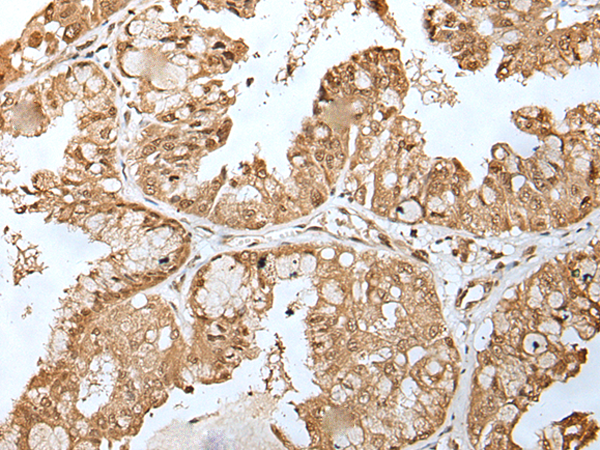

IHC positive control:

Human esophagus cancer and human liver cancer

IHC Recommend dilution:

25-100